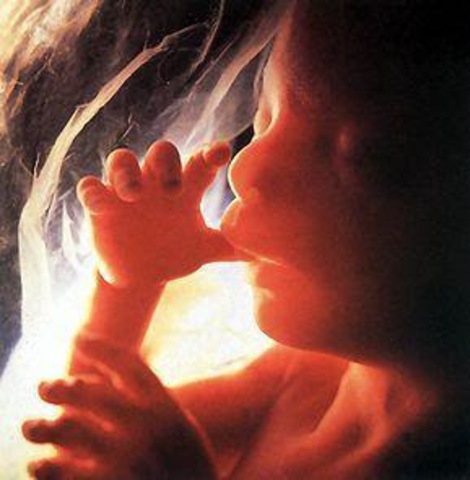

La placenta está definitivamente constituida y produce las hormonas necesarias para el buen desarrollo del embarazo. Las funciones respiratorias del bebé se activan, sus pulmones continúan creciendo y los movimientos respiratorios, aunque todavía bastante irregulares, tienen una frecuencia cada vez mayor. Su pelo y sus uñas siguen creciendo.

Su médula ósea empieza a producir glóbulos rojos